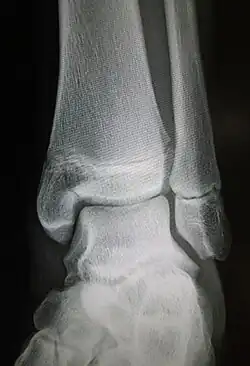

Maisonneuve fracture

| Maisonneuve fracture | |

| Radiograph showing a Maisonneuve fracture of the proximal fibula | |

The Maisonneuve fracture is a spiral fracture of the proximal third of the fibula associated with a tear of the distal tibiofibular syndesmosis and the interosseous membrane. There is an associated fracture of the medial malleolus or rupture of the deep deltoid ligament of the ankle. This type of injury can be difficult to detect.[1][2]